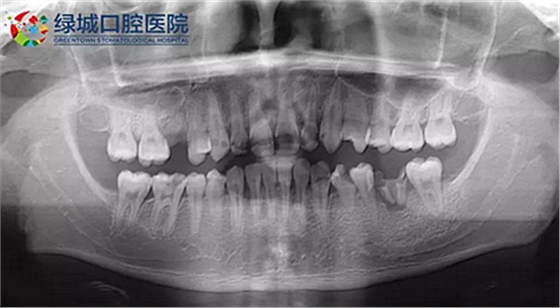

下面是醫(yī)生眼中和ct下的我們

一身病痛啊

牙結石、牙齦炎癥、牙體殘缺、慢性牙髓炎、蛀牙......

下面是醫(yī)生給開出的治療計劃

治療是從5月份開始的,醫(yī)生給我的主人驗了血,做手術前的準備,還給我們都用超聲波好好的都洗了個澡,把之前依附在我們身上的牙結石都沖了個干凈(齦上潔治術)。治療先從我和其他3個兄弟開始。在麻藥的作用下,我們兄弟4個都被打開了身體,去除了已經(jīng)被蛀牙破壞的牙體,做了根管治療。